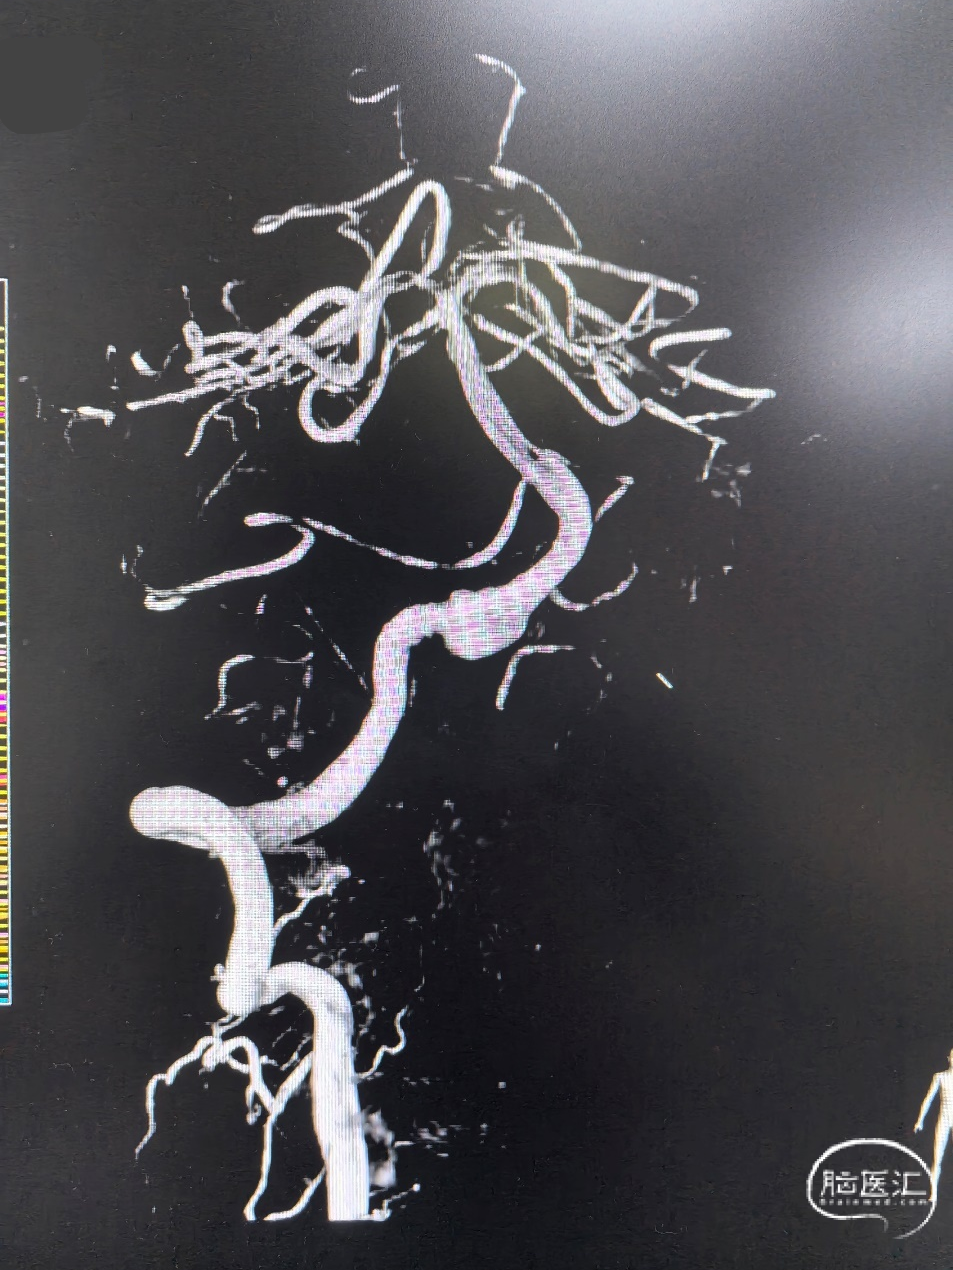

术前3D影像:

DSA正侧位造影显示:右侧椎动脉V4段夹层动脉,瘤颈约8mm,血管直径约3.5mm。

诊断结果:

造影后发现右侧椎动脉夹层动脉瘤,发生部位V4段,夹层远端累及汇合处,动脉路径较为迂曲。

患者治疗后4个月复查,3D成像清晰可见支架贴壁良好,载瘤动脉未见狭窄、夹层病变血管修复良好。